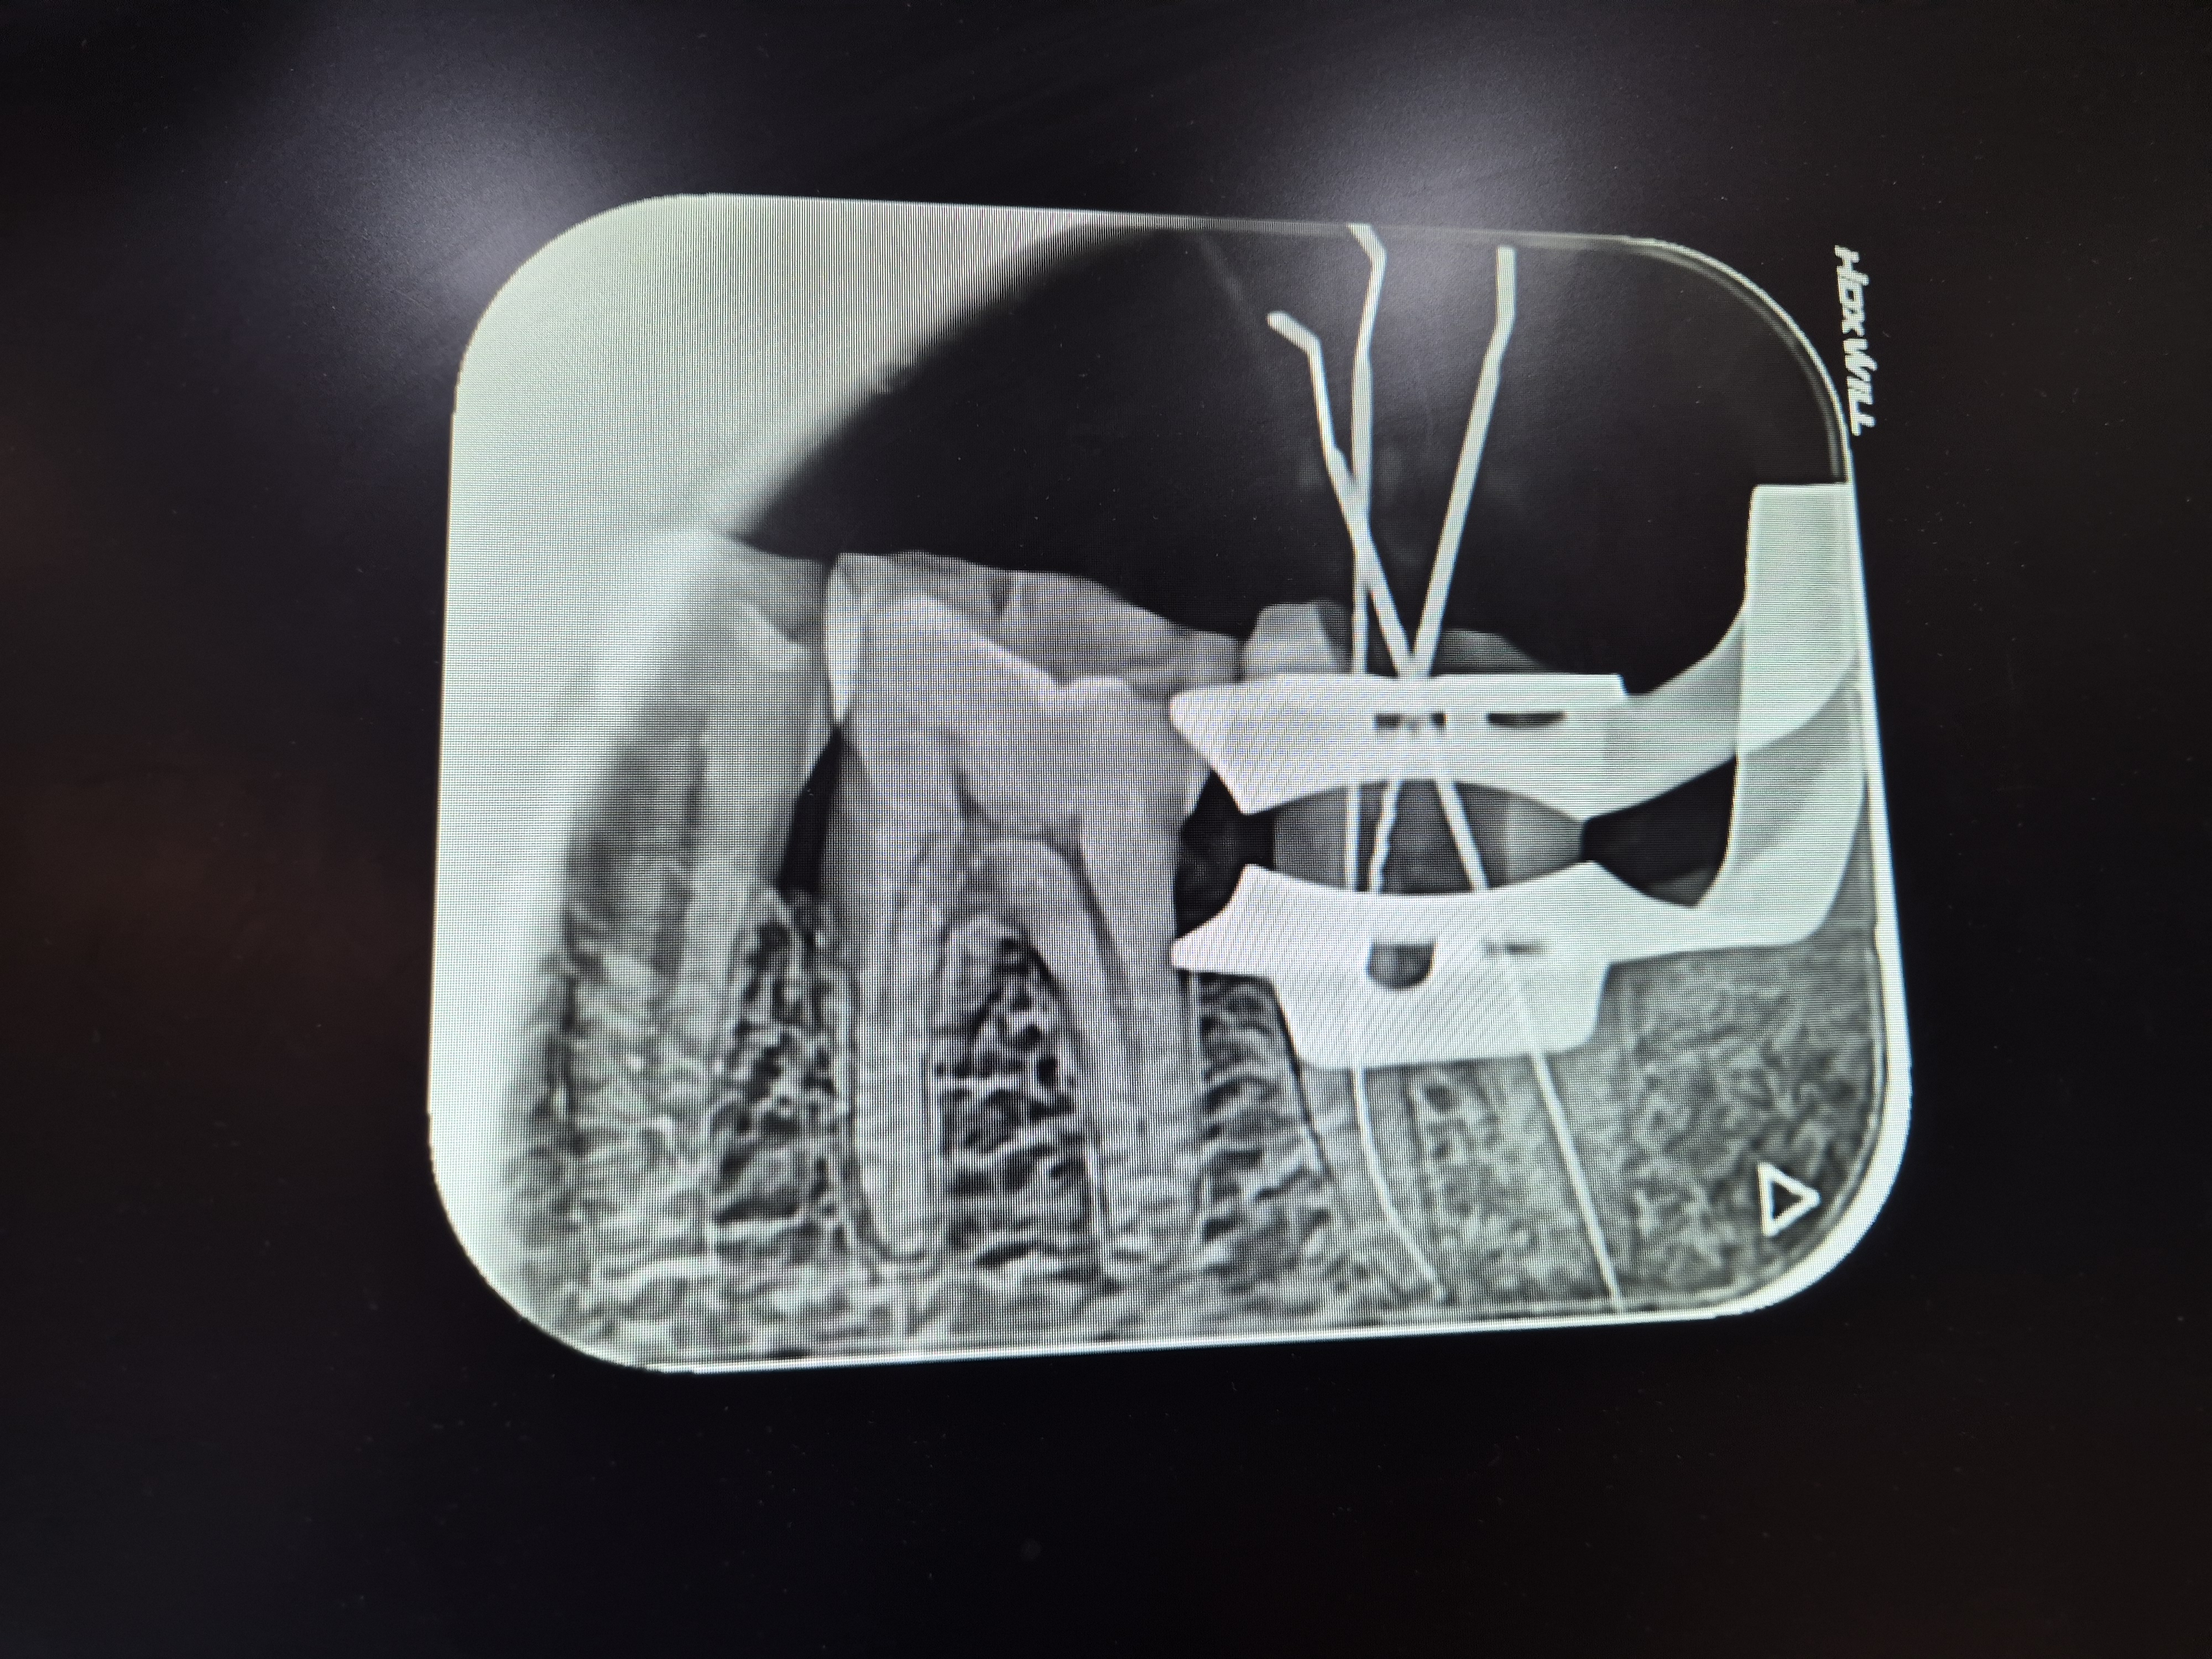

그 후 며칠이 지나도 더욱 아파오니 인근의 병원을 찾아가 사진을 찍고 검진을 받아보니

충치가 생겨 신경치료를 4회정도 받아야한다는 것이다.

마취를 하고 2회정도 치료를 받고는 다시 치료를 2회정도 더 받고는

덧씌워야하는데, 첫치료에서 마취를 하였는데도 치아를 갈아내는데 온몸이

소름이 돋을 정도로 시큼하다.

두번째 치료에서는 그 시간이 길어지니 벌린입이 경련이 생길정도로 아파진다.